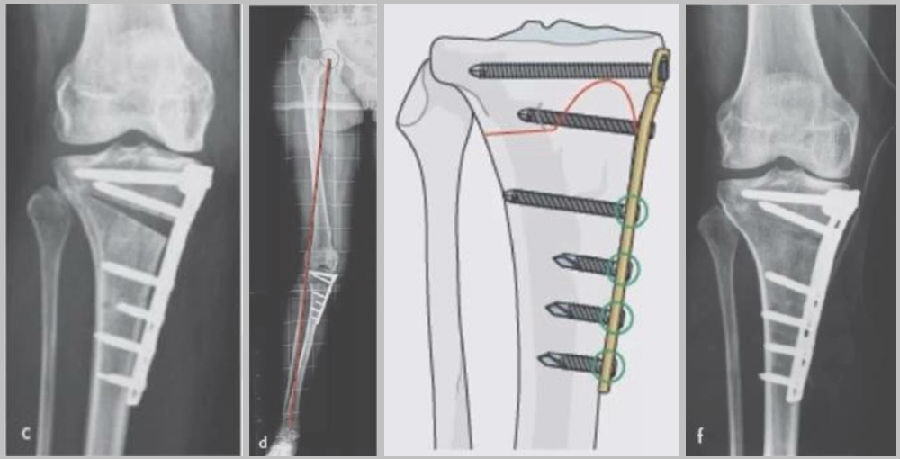

(3)Ⅲ型骨折

首先要把截骨撑开钳拿下来,此时骨折端会自动复位,然后再由外向内侧打入一颗拉力螺钉,将胫骨平台做临时固定,然后再进一步的用摆锯锯或是用骨刀打,保留1cm的合页,最后再进行撑开,做内固定。同样要求患者做结构植骨加延迟负重。

截骨偏前,截骨线过短;Ⅲ型骨折;保留1cm合页

结构植骨,外侧拉力钉固定